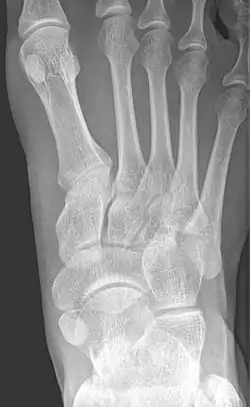

Radiological images

From left to right: Type 1, 2 and 3

Cornuate navicular bone